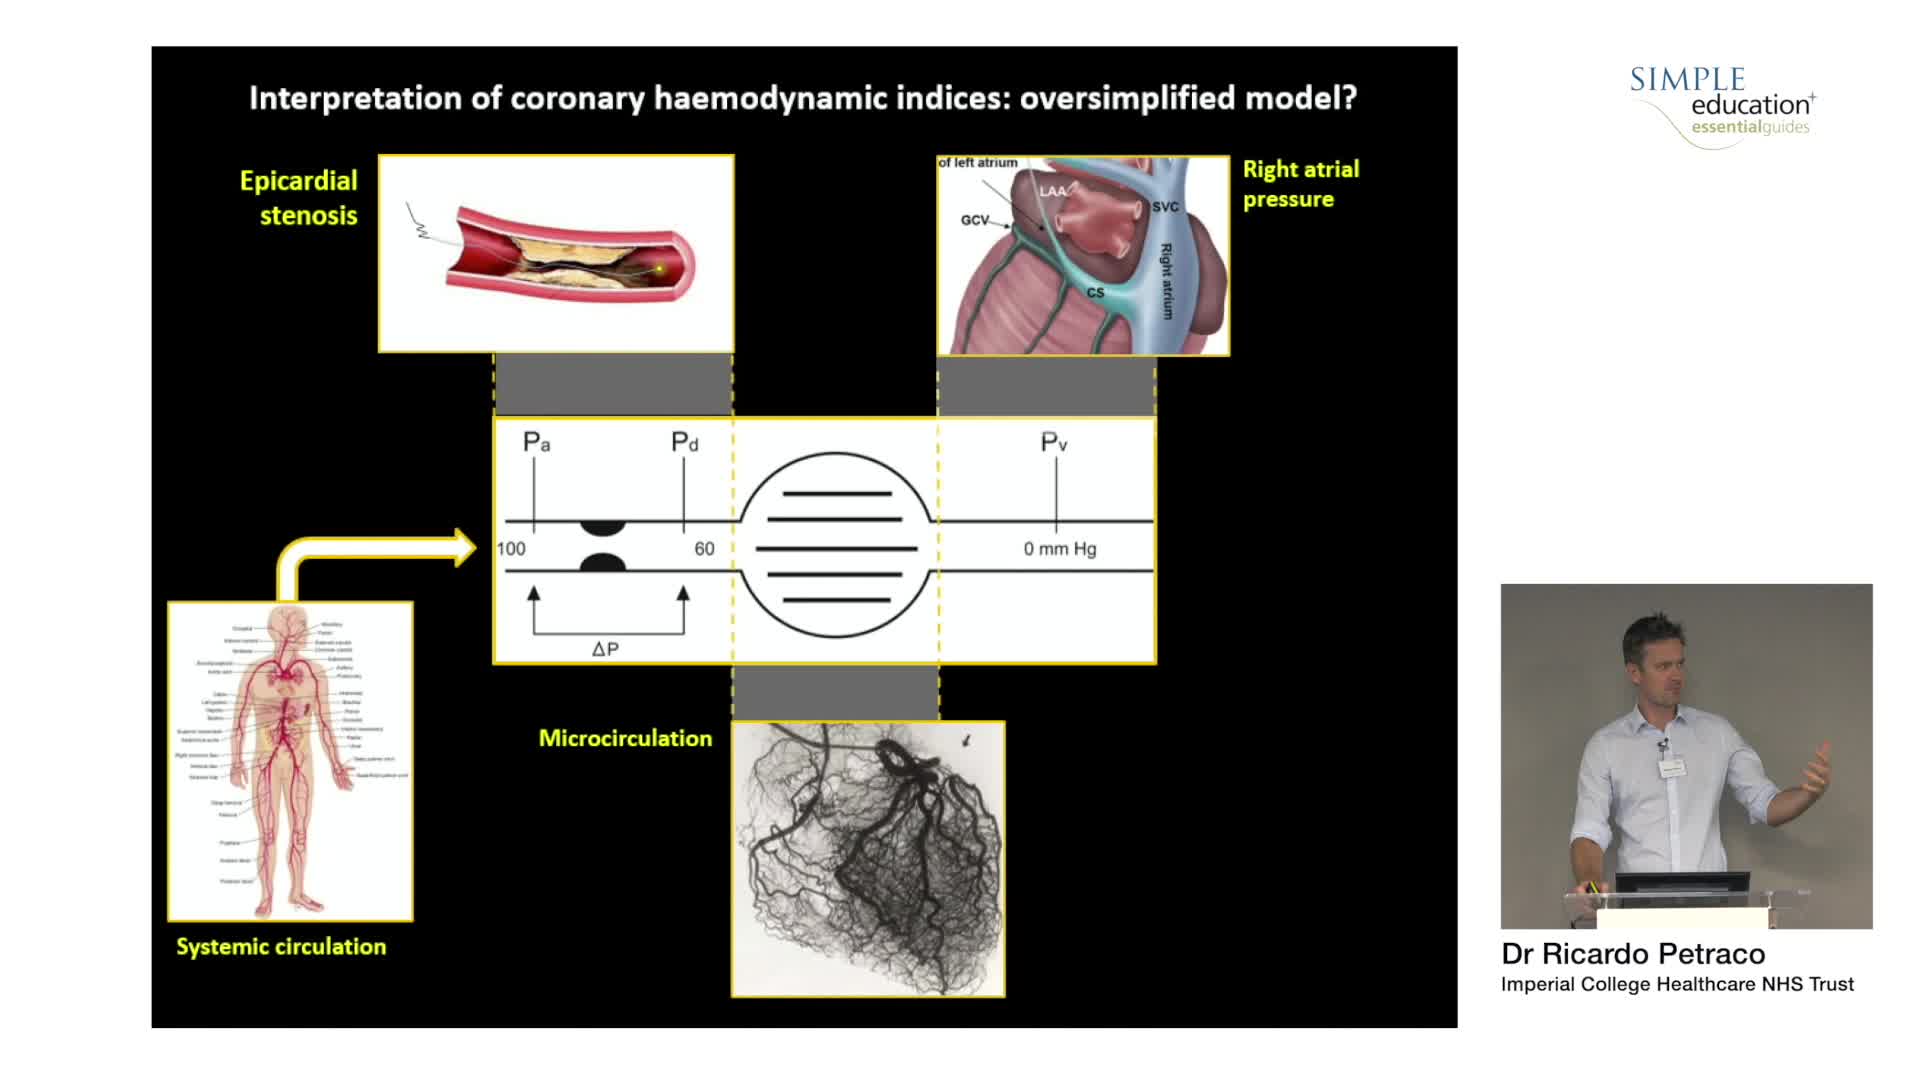

Understanding mechanisms of regulation of resting and hyperaemic blood flow, across single and serial stenoses

How to perform iFR and FFR, and best-practice measurement tips and tricks - Dr Ricardo Petraco

ABC for using Coronary Physiology in Aortic Stenosis, Primary Percutaneous Coronary Intervention (PPCI)/ACS, Muscle Bridges and Atrial Fibrillation - Dr Ricardo Petraco